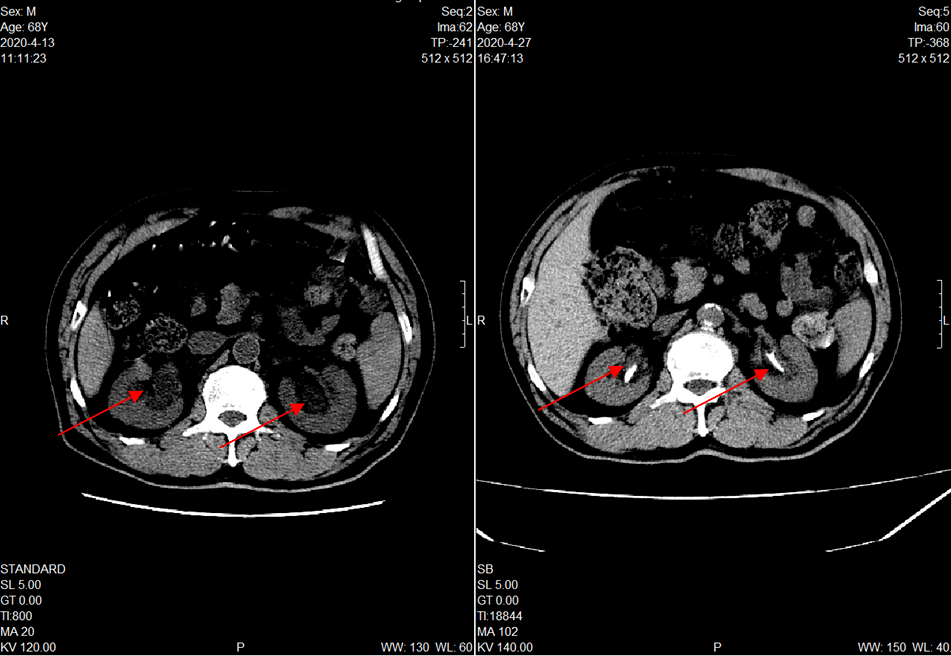

入院后查ct发现肾衰为双侧肾脏结石梗阻所致!双侧肾脏皮质损坏殆尽!